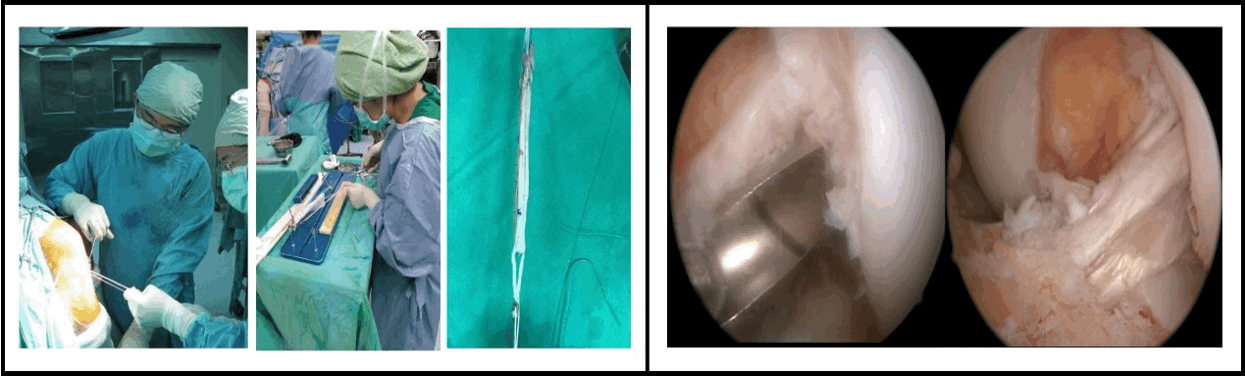

Today, Xiaogang Hospital's orthopedic team has a complete composition and sub-specialties, and is developing in all aspects. There are currently 7 full-time attending physicians. It can provide the people of Southern Kaohsiung with the most comprehensive orthopedic treatment (see details below). For example, pelvic fractures and rib fractures that required referral to higher education a few years ago can now be fully treated in Xiaogang Hospital with the joint efforts of orthopedics, emergency department, operating room, ICU, and thoracic surgery, and gradually formed the Department of Orthopedics of Xiaogang Hospital. Specialized medical care for acute and severe cases. The Department of Orthopedics of Xiaogang Hospital also received the SNQ certification "South Kaohsiung "Hand" Guardian" in 2020, which means that the Department of Orthopedics of Xiaogang Hospital has been recognized for its efforts in reattachment and reconstruction of severed limbs in recent years. The effectiveness and business volume of the Department of Orthopedics of Xiaogang Hospital in shock wave therapy It is also ahead of the system hospitals. In terms of innovative surgery, Xiaogang Hospital's Department of Orthopedics is the first to introduce 3D arthroscopy, which provides doctors with a better surgical field of view and gives patients more precise joint positioning.

- Minimally invasive arthroscopic surgery (shoulder, elbow, wrist, hip, knee, ankle)

2. Anterior cruciate ligament reconstruction, meniscal surgery, knee cartilage reconstruction surgery

3. Minimally invasive surgery for shoulder rotator muscle reconstruction

5. Minimally invasive arthroscopic surgery (shoulder, elbow, wrist, hip, knee, ankle) 3D arthroscopy

b. ACL reconstruction

c. Rotator cuff repair